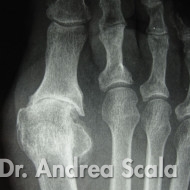

Alluce valgo recidivato o fallimento intervento

IMG 3 – La radiografia mostra che il fallimento dell’intervento dell’alluce valgo si accompagna all’alluce rigido.